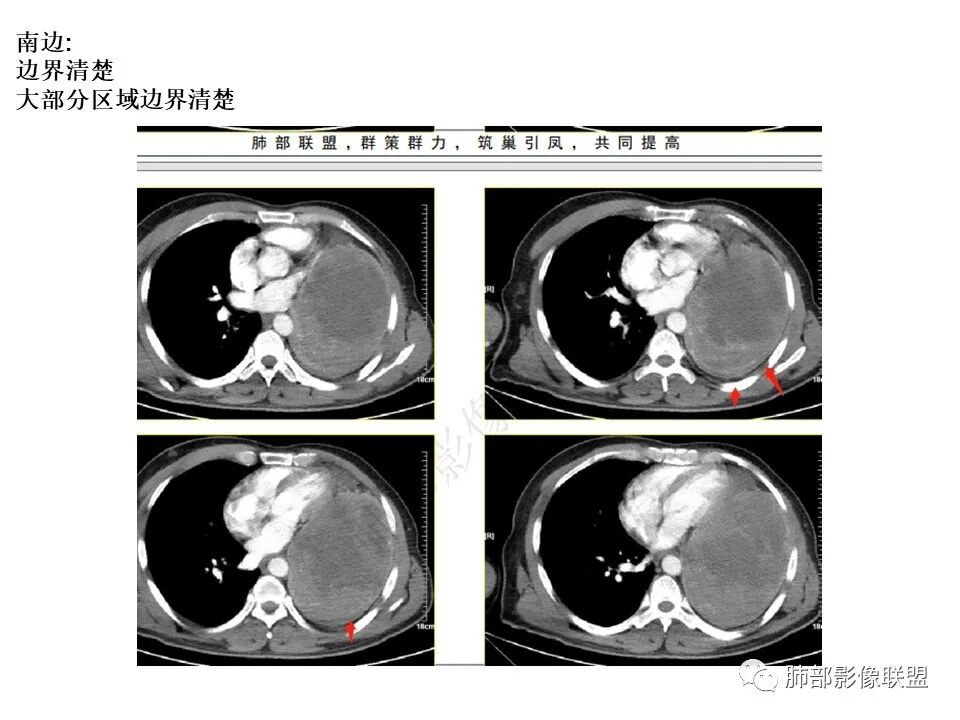

好发于肺胸壁交界区或纵隔交界区,病灶部位对病灶性质判断有较大价值。多单发,有包膜,边界清。

恶性倾向:体积较大,多见出血、囊变及坏死;强化多不均匀;呈浸润性生长,与周围组织器官边界不清;出现远处转移等。

4.病灶紧贴胸壁,胸壁未见栽赃侵入。

5.纵隔左移,左肺门变形。左肺门及纵隔未见明显增大淋巴结。